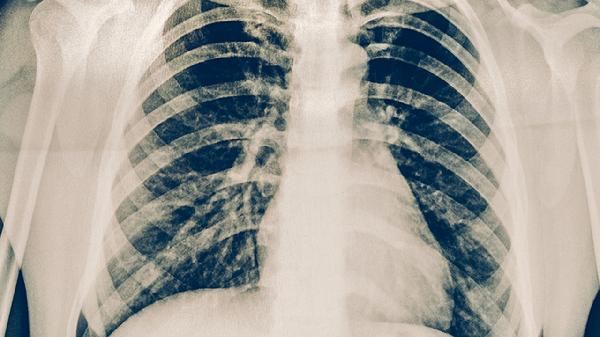

肺结核患者在规范服药期间一般可以游泳,但需满足无传染性、体力允许且水温过低等条件。肺结核是由结核分枝杆菌引起的慢性传染病,抗结核治疗通常需要6-9个月,游泳等适度运动有助于改善心肺功能,但需结合个体状况调整。